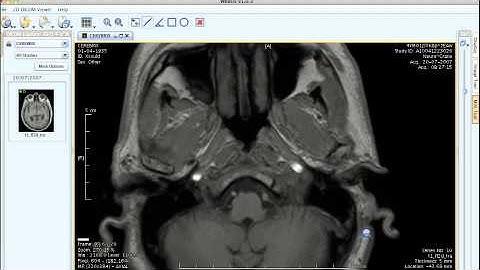

OsiriX - XML/RPC Interface demonstration